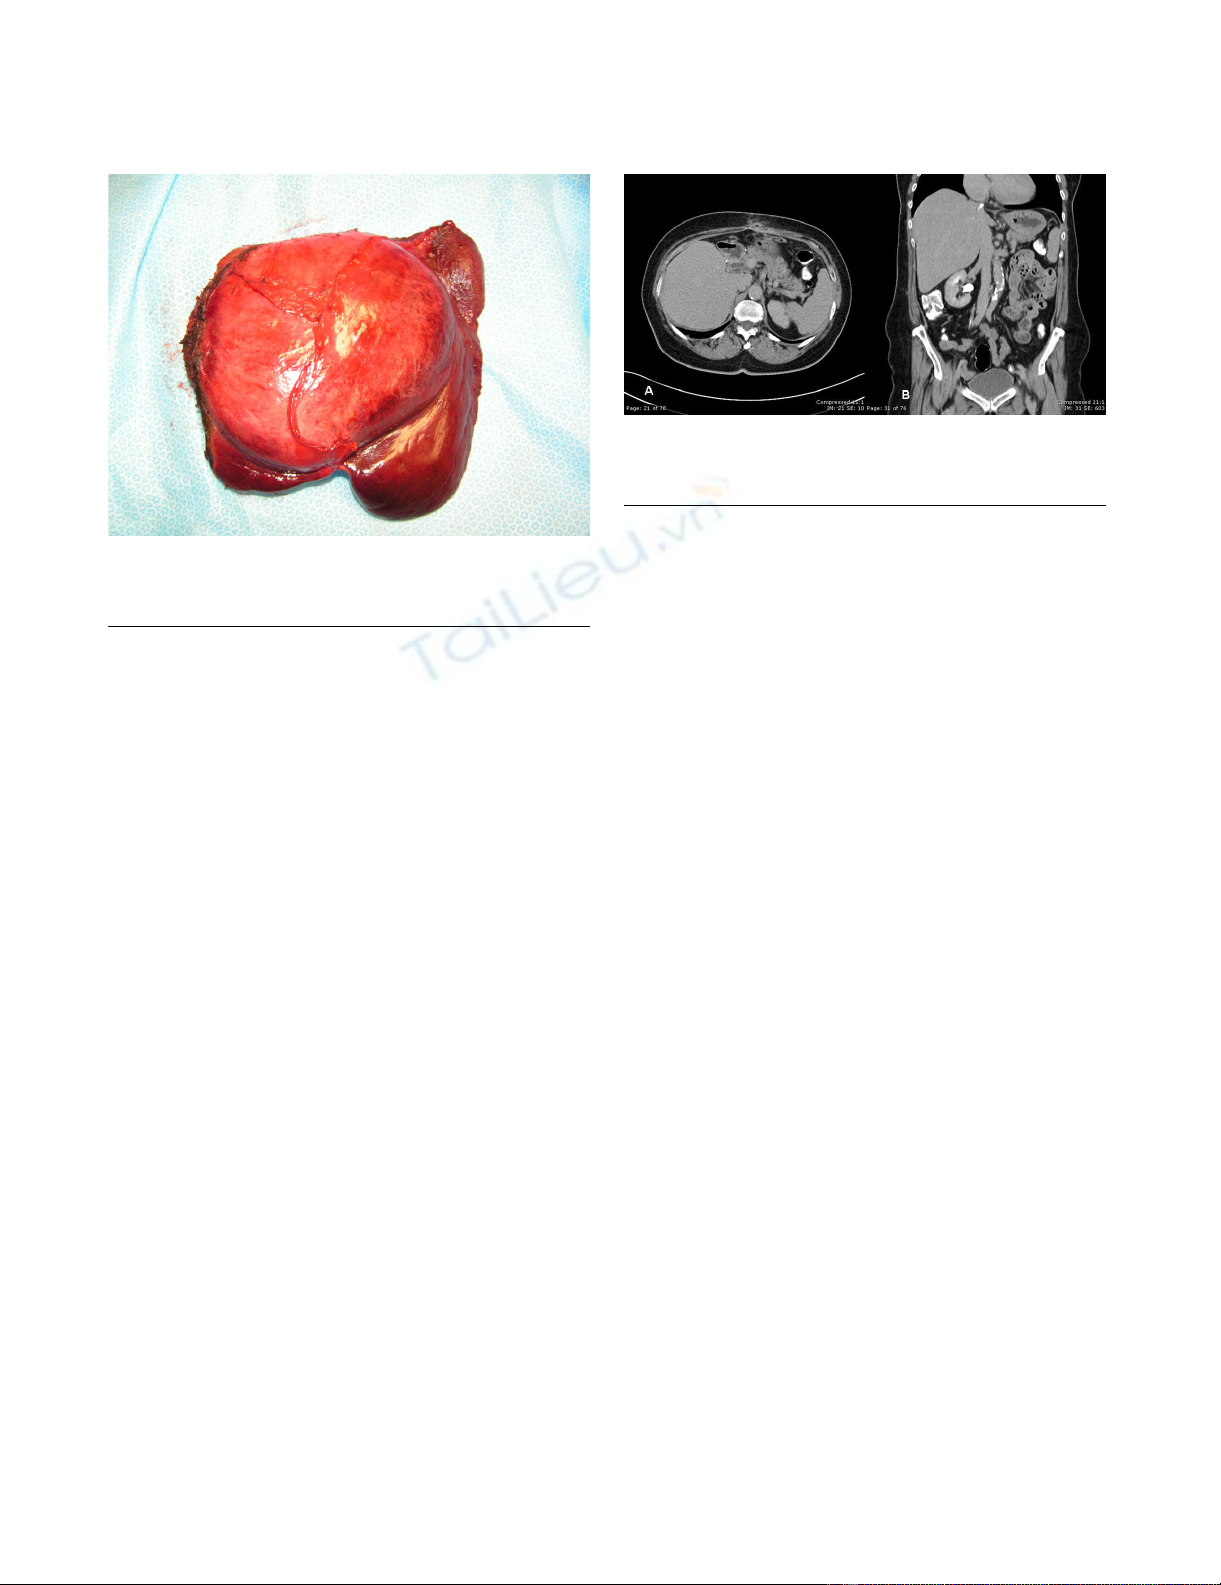

A multidisciplinary and staged treatment course was rec-

ommended. Side effects and benefits of using Imatinib

drug were considered by our tumor board, and the patient

was started at a dose of 600 mg per day to reduce tumor

size. The patient was followed regularly for the next few

months as an outpatient. Her jaundice resolved and the

biliary catheter was successfully removed four months

after placement. A significant clinical improvement was

noted, with resolution of the patient's initial symptoms

and a 7-pound increase in body weight. Frequent abdom-

inal CT scans showed a hepatic mass that diminished in

size, but stabilized after 6 months of imatinib therapy at a

diameter of 11 cm (Figure 2a, 2b).

The patient then underwent portal vein embolization

(PVE) in hopes of promoting hypertrophy of the right

lobe and further atrophy of the tumor-laden left hepatic

lobe, in preparation for surgical resection.

Two months following PVE, while still on imatinib, the

patient underwent an uncomplicated left hepatic lobec-

tomy with cholecystectomy (Figure 3). Intraoperative

ultrasonography showed a hypertrophied right liver lobe,

and a 11 cm tumor involving liver segments 2, 3, 4A an

4B. Pathologic examination corroborated the diagnosis of

metastatic GIST with margins of resection free of tumor.

computerized tomography A) and B); mass in the left lobe of the liver has decreased in size with respect to the prior studyFigure 2

computerized tomography A) and B); mass in the left lobe of

the liver has decreased in size with respect to the prior

study.

left lobe of the liver, with falciform ligament gallbladder and xiphoid processsFigure 3

left lobe of the liver, with falciform ligament gallbladder and

xiphoid process.